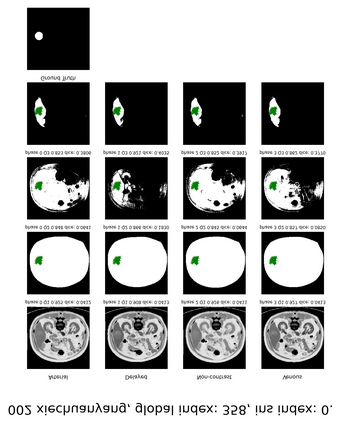

Learning to segmentation without large-scale samples is an inherent capability of human. Recently, Segment Anything Model (SAM) performs the significant zero-shot image segmentation, attracting considerable attention from the computer vision community. Here, we investigate the capability of SAM for medical image analysis, especially for multi-phase liver tumor segmentation (MPLiTS), in terms of prompts, data resolution, phases. Experimental results demonstrate that there might be a large gap between SAM and expected performance. Fortunately, the qualitative results show that SAM is a powerful annotation tool for the community of interactive medical image segmentation.